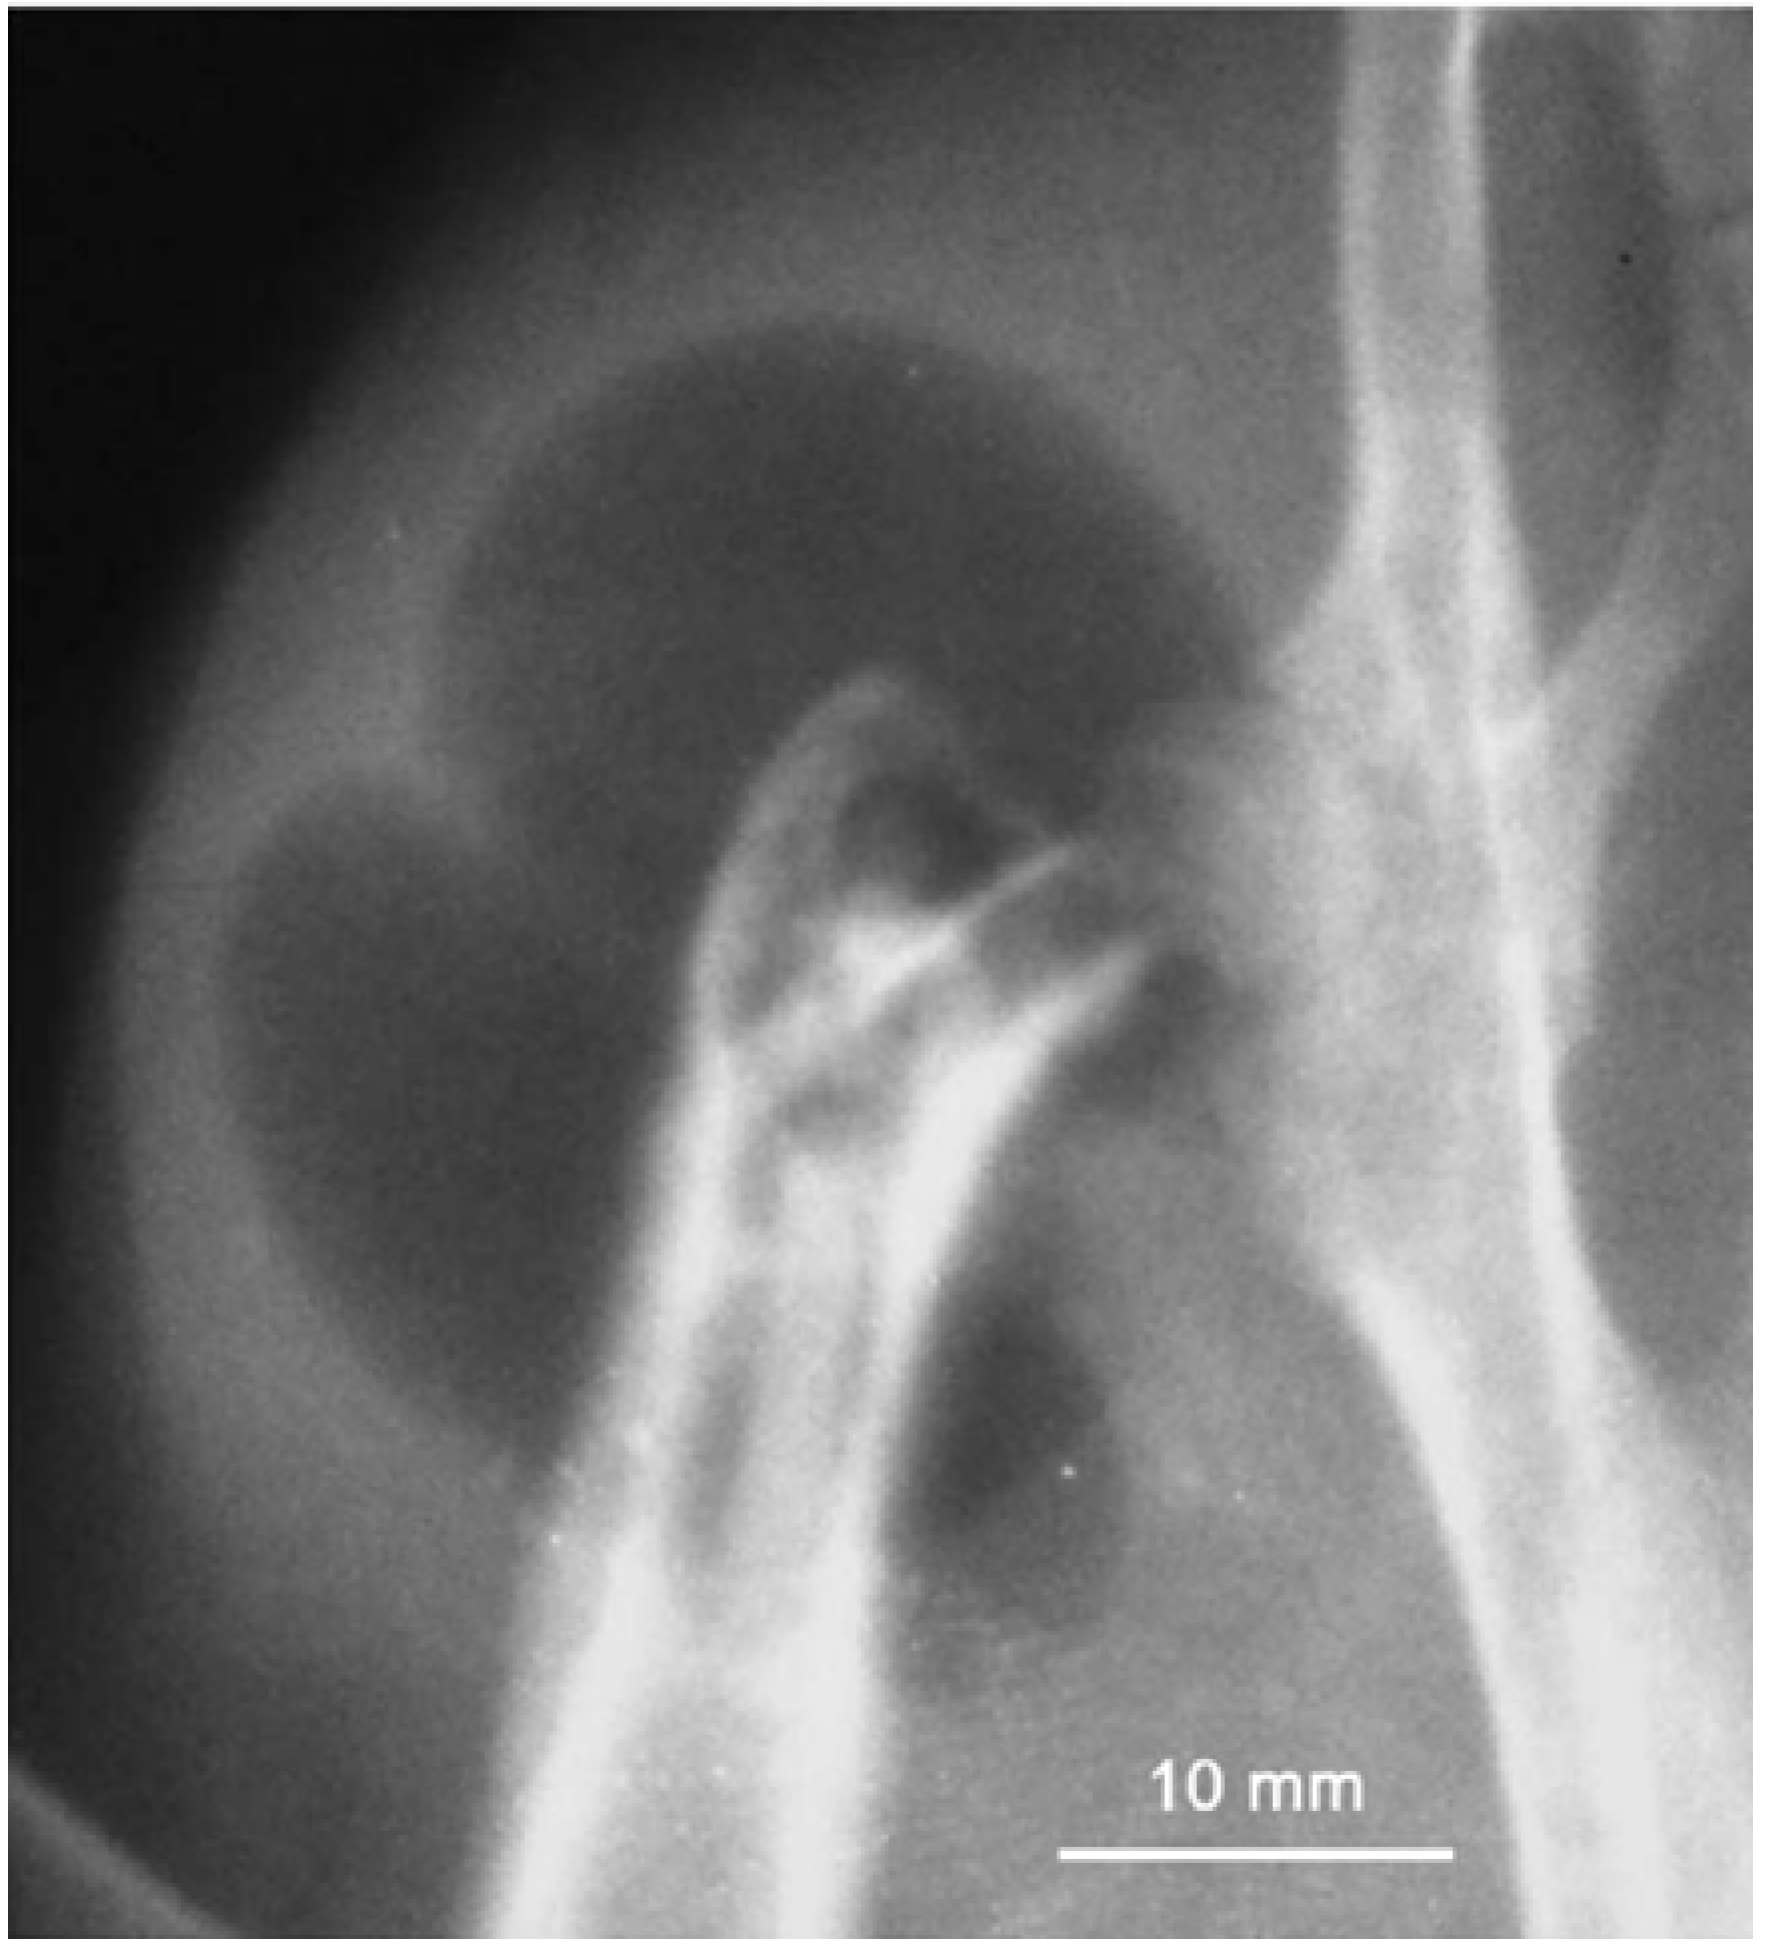

During magnesium dissolution, hydrogen gas is produced and actually hydrogen evolution rate equals to magnesium implant dissolution/corrosion rate. As such, eudiometry of hydrogen has been used as a tool to study long term degradation behavior of Mg-Ca implants in vitro. Corrosion of one gram magnesium results in production of 1.081 liter hydrogen gas [27,68]. The accelerated corrosion will lead to early loss of mechanical integrity and to generate hydrogen at rates too fast for human body to deal with which will result in the formation of subcutaneous gas bubbles [68,69]. Figure 8 shows a typical gas bubble containing hydrogen. As mentioned before, several possibilities exist to adjust the corrosion rate and two of them are using alloying elements and protective coatings. In alloying approach, critical issues are using minimized alloying elements, non-toxic elements, and biological compatibility. Magnesium alloys exhibit different degradation rates depending on the alloying element they contain. Most alloying elements such as aluminum and zinc are suggested to increase the rate of oxidation, while alloying magnesium with rare earth elements is suggested to decrease the oxidation rate of magnesium alloys [68].

Figure 8. Subcutaneous gas bubble observed on postoperative radiographs for 4 weeks during magnesium implant degradation [68].